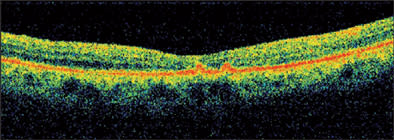

On examination, her vision was light perception in her right eye and barely counting fingers in her left eye. Anterior-segment examination revealed a 1-mm layered hypopyon in her right eye and 3+ cells in her left eye. Posteriorly, she had bilateral 3+ vitreous cells, arteriolar and venous sheathing, extensive intraretinal hemorrhage, retinal edema, and serous retinal detachments (Figure 1).

Figure 1. B-scan ultrasonography of the left eye, revealing significant vitritis, serous retinal detachment, and choroidal thickening. Evaluation of the right eye revealed similar findings.